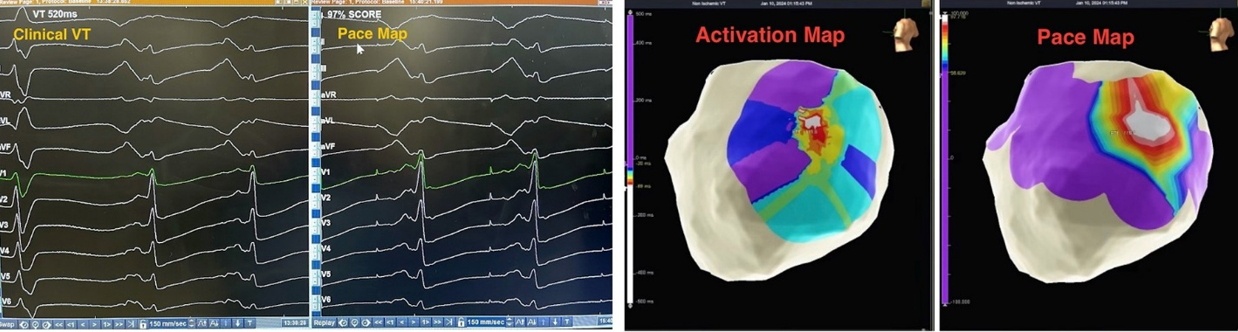

Intraoperatively, clinical VT was induced with pacing maneuvers. Endocardial and percutaneous epicardial maps of the left ventricle (LV) were performed based on the VT morphology and substrate. Under general anesthesia, VT was not sustainable but was repeatedly inducible. Hence, pace mapping was performed to identify the substrate/exit for the clinical VT. Pace mapping on the basal-mid antero-lateral epicardial surface of the LV showed a nearly identical (97%) match to the clinical VT (Figure 2), identifying the exit site.